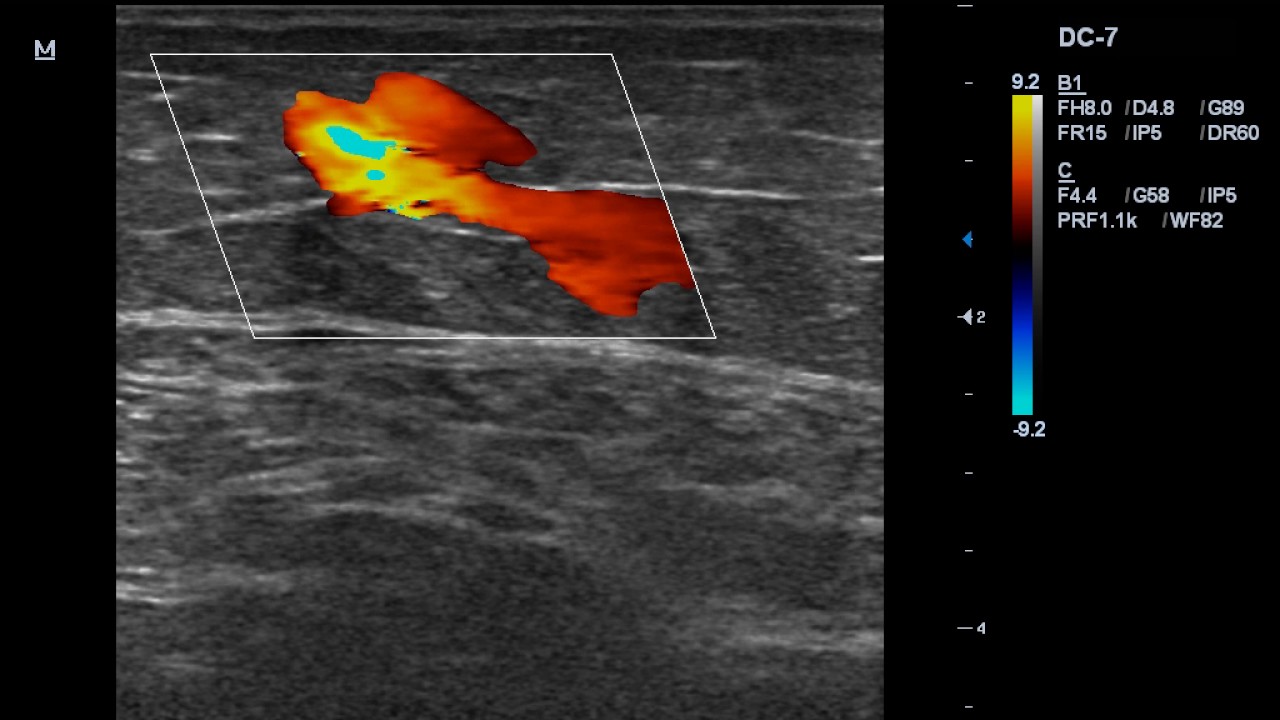

Рефлюкс по венам

Рефлюкс по венам 134 фото